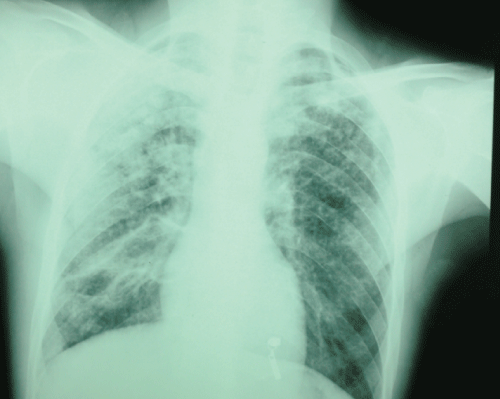

Clinical examination revealed, in nasofibroscopie, tumor in the larynx. There was no neck stiffness or enlarged lymph nodes or signs of meningeal irritation or localising neurological deficit. Chest radiography revealedwide spread small (2-4 mm) nodular opacities distributed throughout both lungs (Figure 1). Direct laryngoscopy revealed a tumor taking all the epiglottis, the two ventricular bands and the two arytenoid (Figure 2), the piriform sinus, the sub-glottis and esophageal mouth are free, basic language is flexible. The biopsy with histological examination revealed chronic inflammation with epithelioid granuloma giant cell without necrosis.

Figure 1: Chest radiography revealed wide spread nodular opacities distributed throughout both lungs.